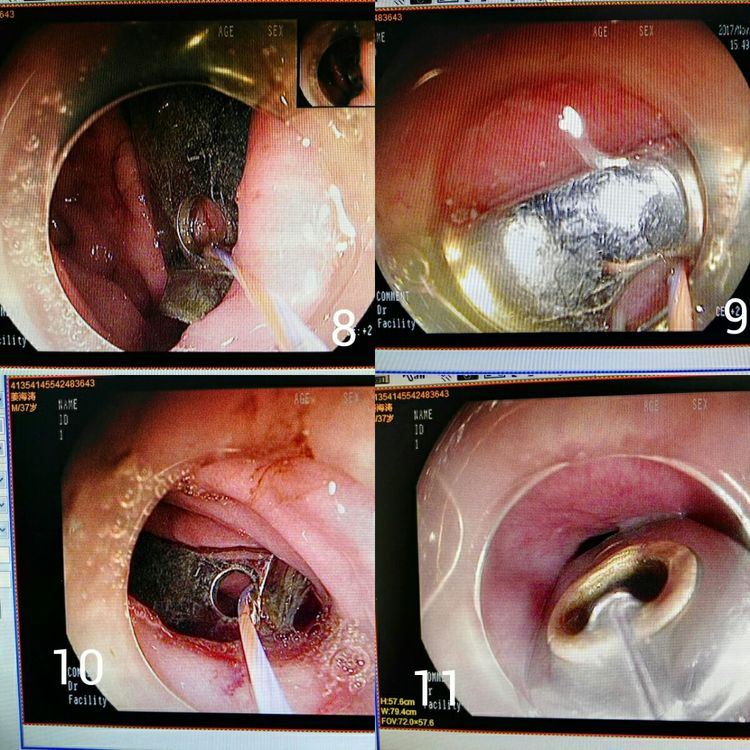

图8、9、10显示已将超柔导丝穿入指甲刀圆孔中,图11可以看出把指甲刀带入透明冒中。